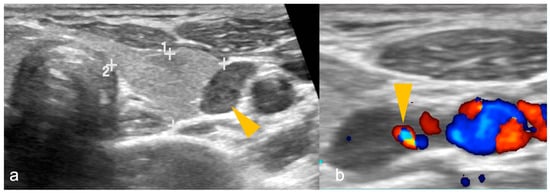

The patient is scanned with mild neck extension using a linear array high-frequency probe (7.5–15 MHz) in transverse and longitudinal planes with a special focus behind the thyroid gland medial to the carotid and jugular vessels where the parathyroid glands are usually located [18]. The neck should be scanned from the carotid bifurcation to sternal notch and the paratracheal spaces, carotid-jugular axis, and thyroid gland should be included [79]. PA is a well-circumscribed, oval- or oblong-shaped, hypoechoic lesion compared to the adjacent thyroid gland, located posterior (more commonly), anterior or lateral to the thyroid at the superior/inferior polar regions, having an echogenic capsule, and shows an enlarged feeding inferior thyroidal artery (feeding vessel sign) on colour Doppler with a low resistive index on spectral Doppler [1,18]. Internal heterogeneity due to fat, calcifications or haemorrhage can be seen [1]. US of a PA is shown in Figure 1.

Figure 1.

(a,b): Parathyroid adenoma on ultrasonography in a patient with primary hyperparathyroidism. (a) A well-defined oval-shaped homogeneously hypoechoic lesion (arrowhead) lateral to the left lobe of thyroid gland (shown by 1, 2 and + sign). (b) Colour Doppler image shows feeding vessel sign (arrowhead). Imaging findings are suggestive of parathyroid adenoma.